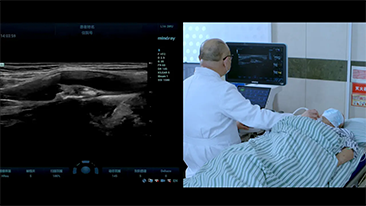

Covid-19 - Pr├│ba si? dla ludzi i aparatury

W zwi?zku z pandemi? koronawirusa szpitale i personel medyczny opracowa?y nowe praktyki robocze obejmuj?ce post?powanie w sytuacjach dotycz?cych stanów ostrych, dystans spo?eczny, rygorystyczne stosowanie ?rodków ochrony indywidualnej (?OI), mycie r?k i codzienn? dezynfekcj? sprz?tu. Dodatkowo w punktach opieki medycznej coraz wi?ksze znaczenie zacz?? mie? przeno?ny, wysoce mobilny i wszechstronny sprz?t, przydatny zw?aszcza w sytuacji, gdy oddzia?y i bloki operacyjne s? rozmieszczone na kilku pi?trach, a dost?p do specjalistycznych urz?dzeń jest ograniczony.